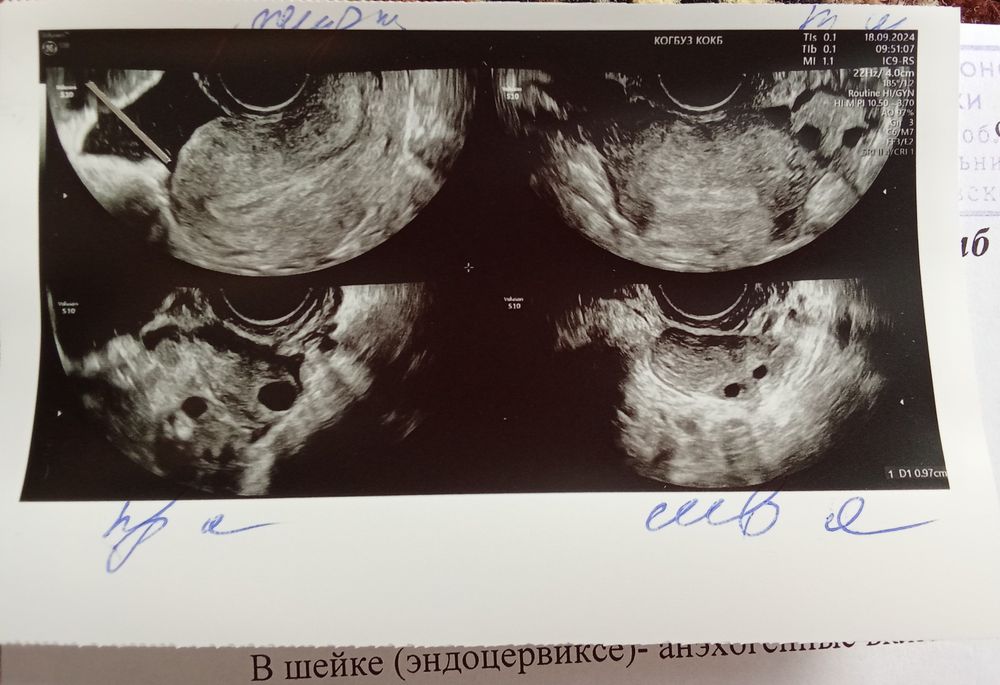

Подскажите пожалуйста что это значит ? Есть ли беременность? Задержка 3-4 дня. На тесте слабая вторя полоска. К гинекологу записана в понедельник, боюсь до понедельника накручу себя😅

Разве в протоколе есть что нибудь о беременности? Нет, увы.

Даже эндометрий слабый. И нет ни доминантного фолликула, ни жёлтого тела. Наличие жидкости может быть признаком состоявшейся недавно овуляции, но это в динамике надо смотреть.

По УЗИ нет ни жт, ни ДФ. Будто овуляция была вчера только. Эндометрий тонкий.

На 1 УЗИ ничего о беременности,а вот на второй это что двойня ?